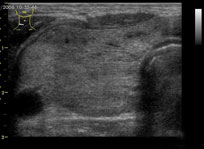

甲状腺超声

甲状腺超声甲状腺超声检查、甲状旁腺超声检查是使用B超对甲状腺、甲状旁腺进行B型超声检查。

(一)甲状腺的厚度(前后径)及宽度(左右径)标准测量切面:在甲状腺的一系列横断面中选择甲状腺实质最厚和最宽处为标准切面,要求探头压力要尽可能轻。 医学百科网 | YxBaike.Com

测量位置:分别选在甲状腺最厚和最宽处的包膜高回声线边缘上。

正常成人参考值(cm):左右两叶厚度各为1.5~2.0cm,宽度2.0~2.5cm,峡部厚度小于0.5cm。

标准测量切面:在甲状腺的一系列纵断面中选择甲状腺实质最长处为标准切面,要求探头压力要尽可能轻。

测量位置:分别选在甲状腺最长处的包膜高回声线边缘上。

正常成人参考值(cm): 左右两叶长度各为4.0~6.0cm,峡部长度1.5~2.0cm。 医学百科网 | YxBaike.Com